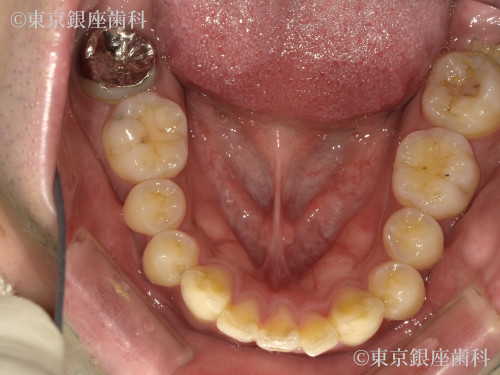

Before

側方前突